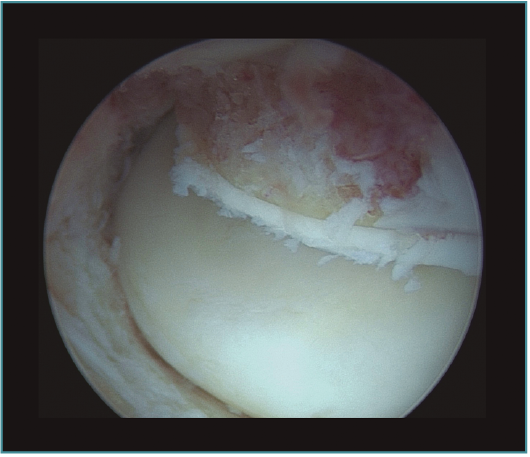

La capsulotomía anterior la iniciaremos de medial a lateral, aproximadamente un centímetro proximal a la punta de la coronoides, utilizando un vaporizador "de gancho" (instrumento que nos parece muy útil para esta tarea, ya que nos permite controlar muy bien la profundidad de la resección de la cápsula para evitar lesionar estructuras neurovasculares próximas); también utilizamos la pinza Basket para resecar la cápsula, sobre todo en los casos en los que está muy engrosada y endurecida (Figura 7). Para disminuir el riesgo de lesión del nervio interóseo posterior (que queda cerca de la cápsula anterior al nivel de la cabeza del radio), dejamos intacta o parcialmente resecada la cápsula sobre la cabeza radial y completamos la capsulotomía con una extensión forzada del codo. Una vez hemos completado la capsulotomía anterior, veremos el tejido muscular del músculo braquial (Figura 8). En este momento no es recomendable resecar más hueso o tejidos blandos por diferentes motivos: al no tener la protección de la cápsula anterior, las estructuras vasculonerviosas están en mayor riesgo de lesionarse; además, en los casos de rigidez el músculo braquial puede ser más delgado, debido a atrofia muscular(14). Otro motivo es evitar el sangrado del músculo, para disminuir el riesgo de aparición de calcificaciones heterotópicas. En caso de ser necesario resecar hueso tras la capsulotomía, emplearíamos un separador a través de un portal anterolateral accesorio y el sinoviotomo o la fresa sin aspirador conectado (Vídeo, minutos 1:36-2:46).

Figura 7. Visión artroscópica desde el portal anteromedial de la realización de una capsulotomía anterior del codo. Vemos la cabeza del radio en la parte más lateral y el músculo braquial en la parte más medial. Apreciamos el grosor de la cápsula anterior en este caso de rigidez postraumática.

Figura 8. Visión artroscópica desde el portal anteromedial del músculo braquial al completar la capsulectomía anterior.